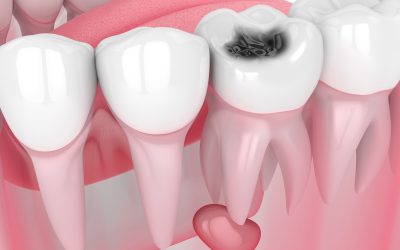

Cisti dentale: cause e sintomi

La cisti dentale è una formazione patologica che si sviluppa generalmente all’apice di un dente a seguito di un’infezione non trattata. Si presenta come una cavità contenente liquido, delimitata da una membrana, e può rimanere asintomatica oppure causare dolore, gonfiore e complicanze più gravi. Nella maggior parte dei casi deriva dalla necrosi della polpa dentale, spesso causata da carie profonde, che inizialmente provocano pulpiti e successivamente la morte del nervo. Se non curato, il granuloma che si forma all’apice del dente può evolvere in una vera e propria cisti, arrivando anche a compromettere la sopravvivenza del dente interessato.